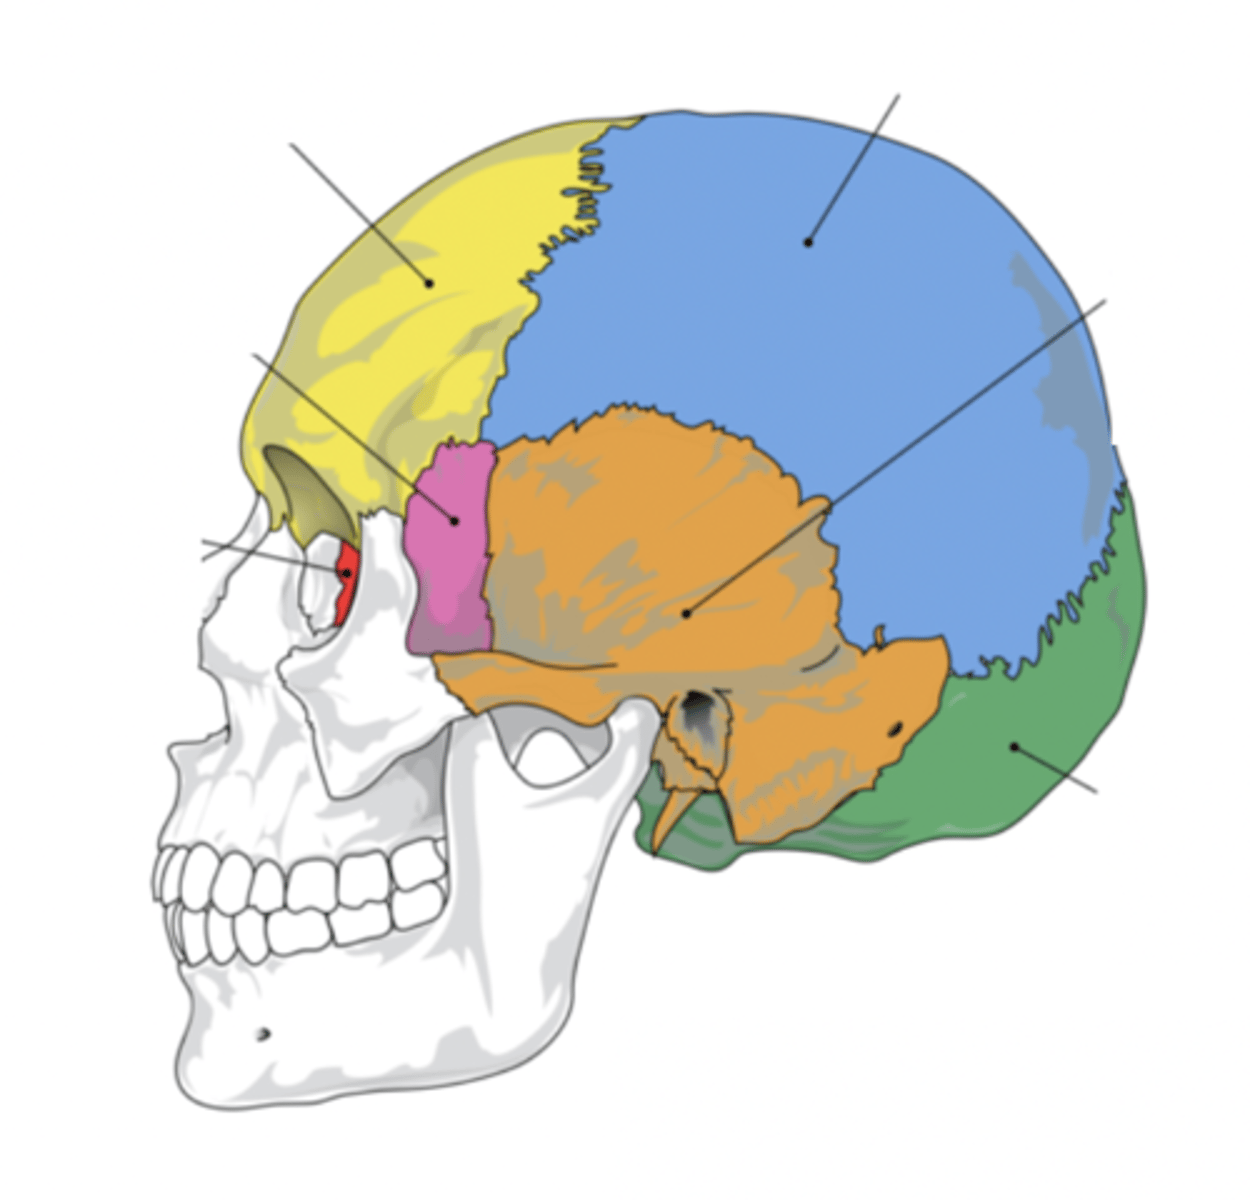

Cranial Bones (8)

- Ethmoid

- Frontal

- Sphenoid

- Temporal (2)

- Occipital

- Parietal (2)

(EFSTOP)

Ethmoid Bone

Forms part of the posterior portion of the nose, the orbit, and the floor of the cranium (red)

Frontal Bone

Bone that forms the forehead (yellow)

Sphenoid Bone

Forms part of the base of the skull and parts of the floor and sides of the orbit (pink)

Temporal Bone (2)

Bone that forms parts of the side of the skull and floor of the cranial activity (orange)

Occipital Bone

Bone that forms the back of the head (green)

Parietal Bone (2)

Either of two skull bones between the frontal and occipital bones and forming the top and sides of the cranium (blue)

4 Main Sutures of the Skull

- Saggital

- Lamboid

- Coronal

- Squamous

(SLCS)

Saggital Suture

Suture that separates the left and right parietal bone

Lamboid Suture

Suture between the occipital and parietal bones

Coronal Suture

Suture between the parietal and frontal bones of the skull

Squamous Suture

Suture between parietal and temporal bones